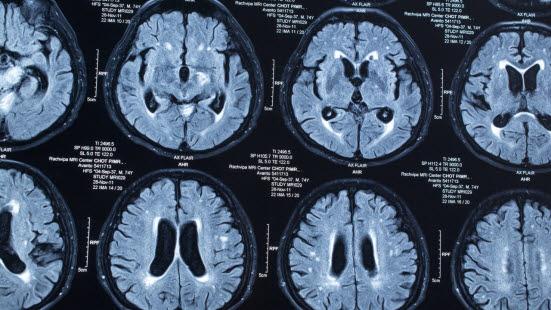

- På sykehuset vil det bli gjort CT